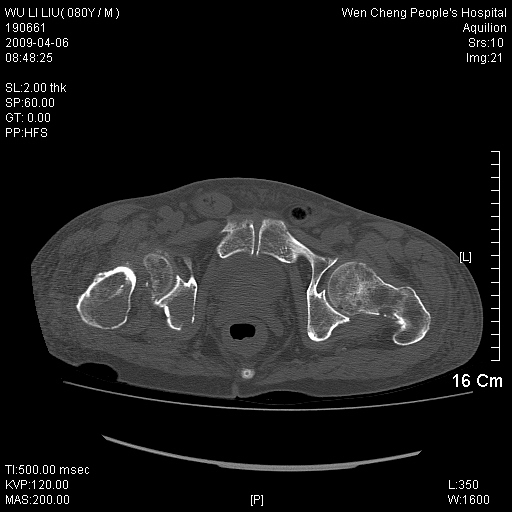

以下是引用zjzjr在2009-4-7 12:13:00的发言:[br]支持多发性转移瘤,右股骨颈骨折,腰椎亦有压缩性骨折.肝内胆管结石伴胆内外胆管扩张,左肾结石.

以下是引用liaoqiang在2009-4-7 8:44:00的发言:[br]考虑多发性骨髓瘤伴肝肺转移、肝内胆管结石、左肾结石、右股骨颈骨折。

以下是引用余辉在2009-4-7 8:52:00的发言:[br]椎骨及骨盆骨质疏松,骨破坏主要累及椎体,各骨破坏较广泛,各病灶边缘均较清晰锐利,血沉增快,白细胞增高.支持考虑多发骨髓瘤,建议查本尿周氏蛋白.[br]胆内胆管及左肾结石[br]右股骨颈骨折,考虑病理性